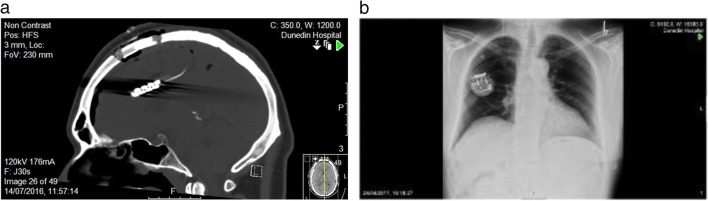

In the operative phase (phase 3), participants had routine pre-operative evaluations and MRI. Using MRI neuro-navigation, two Lamitrode 44 electrodes (Abbot, Neurodivision, Plano, Texas) were placed on the dACC under general anaesthesia (Fig. 1), followed by overnight observation in a neurosurgical high dependency unit.

Fig. 1.

Post-surgical computed tomography (CT) showing (a) the ‘back-to-back’ paddle sutured electrode on the rostrodorsal anterior cingulate cortex (dACC) and (b) the internal pulse generator (IPG) in the chest subcutaneously below the right clavicle